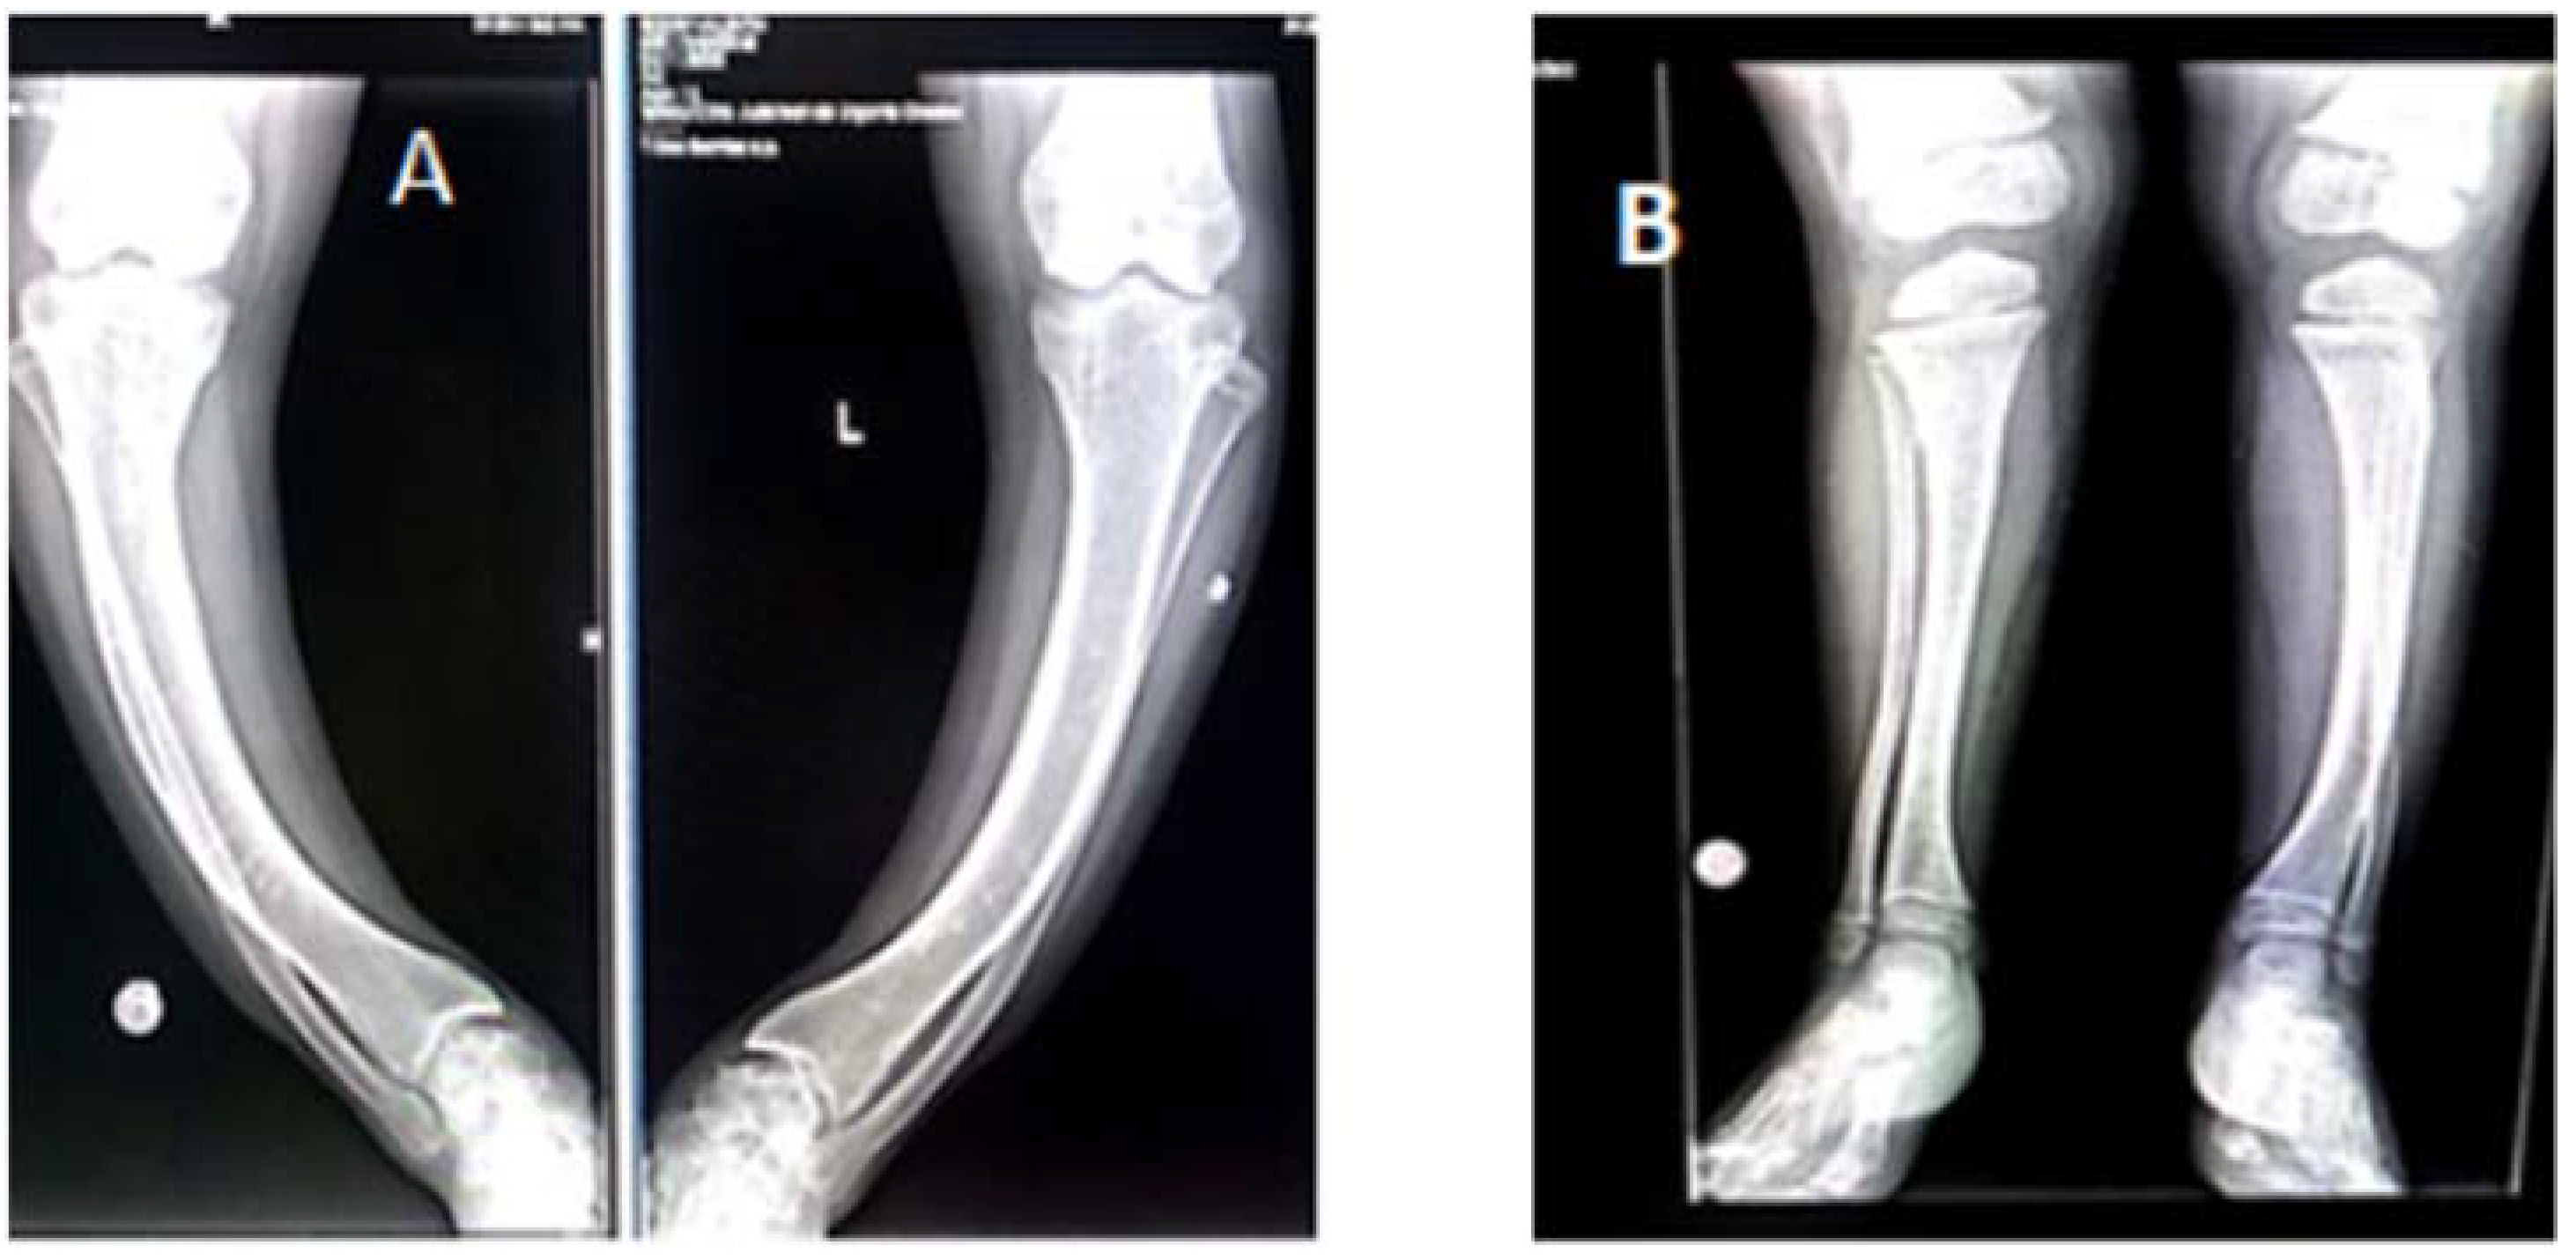

3.3. Radiological Investigations

| Case# 1 | Chest: discrete dextroconvex dorsolumbar scoliosis Bilateral femur: bilateral femural scoliostosis, bilateral enlargement of the distal metaphysis and epiphysis. Bilateral knee, leg, ankle: major bilateral tibial scoliostosis; mild bilateral fibular deformation. Bilateral enlargement of the proximal and distal tibial epiphysis and metaphysis Bone demineralization of the radiographed skeleton, with fine opaque lines Bone age corresponds to chronological age | Bilateral femural scoliostosis (in varum); Marked bilateral tibial scoliostosis; mild bilateral fibular deformation. Closed growth plates. Bone age corresponds to chronological age |

| Case # 2 | Chest: Marked bilateral widening of the anterior ends of the ribs. Costal rosaries. Femur: Deformed, curved femoral diaphysis, widened distal metaphysis and irregular contour at growth plates level. Deformed, curved fibular and tibial diaphysis with widened metaphysis and irregular contours Bone age corresponds to chronological age | Bilateral femoral scoliostosis (in varum); Widened femoral metaphysis In varum scoliostosis of the left tibia, in valgum scoliostosis of the right tibia. Bone age corresponds to chronological age |